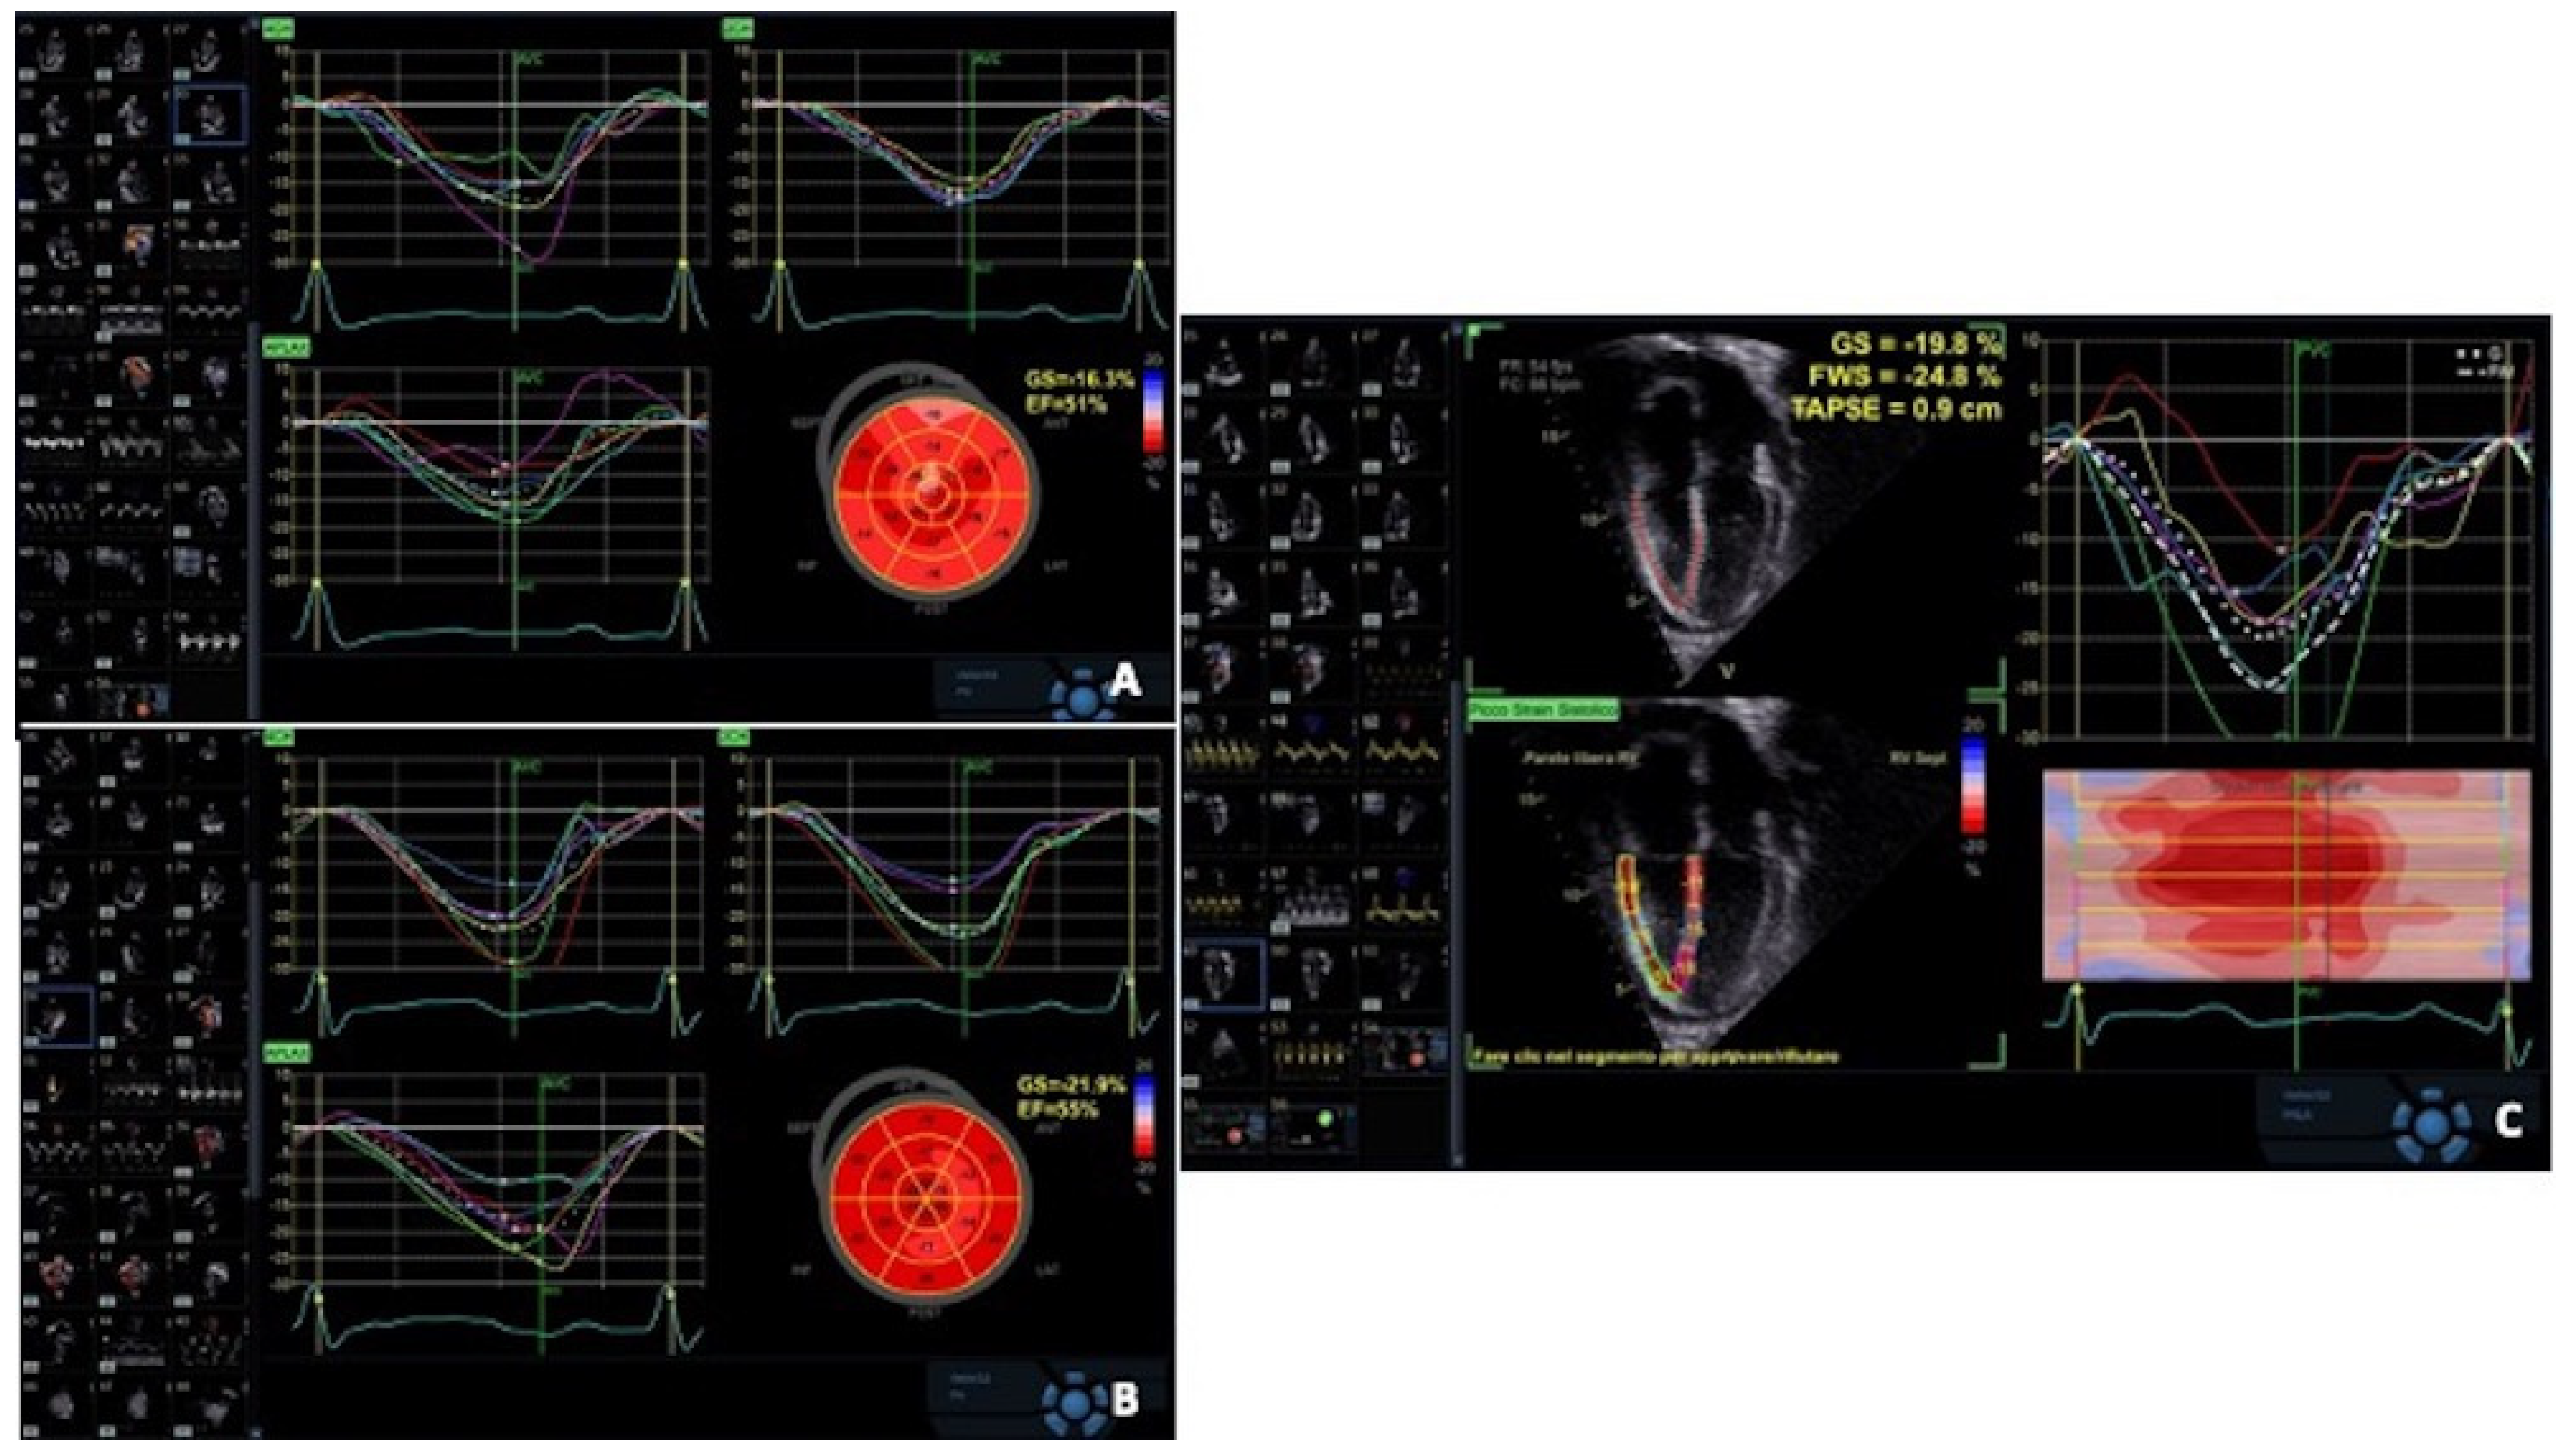

| Mingo-Santos et al. [57] | LV GLS < 15.5% RV FW < 17% LV + RV | 34 | ≥2R | 85.7 85.7 100 | 91.1 81.4 77 | 98.8 98.8 100 |

| Antonczyk et al. [58] | 4CH LS ≤ 13.8% RVFW ≤ 16.8% | 45 | ≥2R | 87 73 | 72 82 | 97 95 |

| Clemmensen et al. [76] | FS, TT and S’ GLS Decreased LVEF | 198 | 92.7% 94.5% | 42.0% 24.6% | 71.6% 66.4% |

| Bjerre et al. [97] | LV-GLS and CFR | 98 | 84.2% | 67.5% | 94.5% |